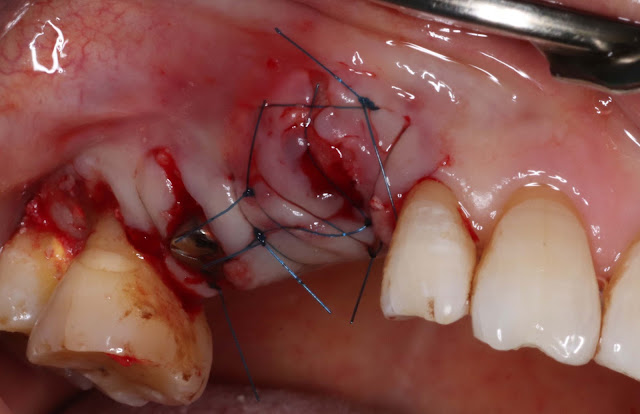

Tooth number 13 was extracted by carefully placing the drill on the palatal side of the root and directly drilling to remove the tooth cautiously.

Implant placement for tooth number 3 was done on the palatal side because the contralateral alveolar bone was thin, making it a suitable location for the implant.

Bone grafting with allograft was performed on the contralateral side during the extraction.

After maintaining the resorbable membrane, the suturing was performed to minimize the exposure of the contralateral flap while keeping it protected.